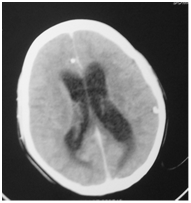

Imaging is required to rule out concomitant intracranial complications, or evidence of increased intracranial pressure. CT scan may show ventricular dilatation (Figure 10). In cases of otitic hydrocephalus, an MRI and magnetic resonance venogram should be performed to evaluate for ventricular enlargement, or coexisting intracranial complications, such as significant sinus thrombosis with obstruction. Magnetic resonance venogram will also confirm the presence of lateral sinus thrombosis, but is not required to make a diagnosis of otitic hydrocephalus.

Figure 10 CT scan showing dilated ventricles.